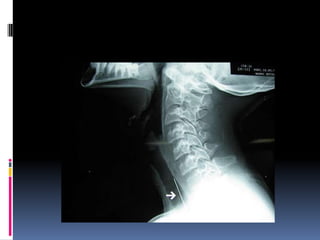

 Estudios Radiológicos.-

 Rx. Simple de Esófago Cervical vista Lateral.

 Rx. DeTórax AP. y Oblicuo.

Localización • Inmediatamente pordebajo del músculo cricofaringeo. • Encima de la unión gastroesofágica. • En los relieves que establecen el cayado de la aorta y el bronquio principal izquierdo.

Diagnostico  Estudios Radiológicos.- Rx. Simple de Esófago Cervical vista Lateral.  Fluoroscopía de Esófago con mota de algodón  Embebida en bario.  Rx. DeTórax AP. y Oblicuo.  Exploración Endoscópica.